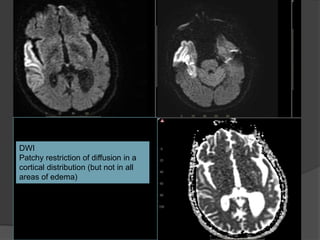

DWI

Patchy restriction of diffusion in a

cortical distribution (but not in all

areas of edema)

Case 2 Diagnosis: MELAS

 MELAS (mitochondrial encephalopathy with lactic

acidosis and stroke-like episodes

 Characterized by 'stroke-like' episodes, typically in

childhood or early adulthood (90% present before 40

years of age)

 Encephalopathy, seizures, dementia, lactic acidosis ,

muscle weakness

 CT: Atrophy, multiple infarcts involving multiple vascular

territories. Parieto-occipital and parieto-temporal

involvement is most common, basal ganglial calcification

• MRI: Swollen gyri with increased T2 signal, increased

signal on DWI (T2 shine through) with no change on ADC

indicating vasogenic edema

• MR spectroscopy: Elevated lactate